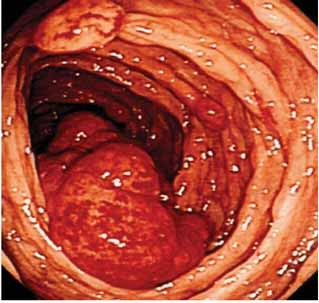

relativně častá anémie. Gastrointestinální trakt a Waldayerův okruh

jsou postiženy až u 1/3 pacientů. Typickou extranodální lokalitou

postiženou infiltrací MCL je střevo. Zde choroba vytváří tzv.

mnohotnou lymfomatózní polypózou, ta se však většinou projevuje jen

nespecifickými příznaky a proto nebývá často diagnostikována.

Obr.7: Endoskopický obraz mnohotné lymfomatozní polypózy u

nemocného s infiltrace střeva lymfomem z plášťových

buněk.